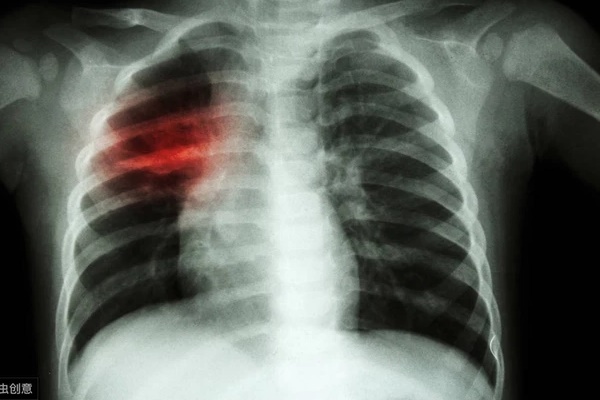

Những món xào nấu luôn được các gia đình ưa chuộng bởi hương vị thơm ngon, đậm đà, hấp dẫn hơn hẳn các món luộc, hấp. Mặc dù vậy, những món ở dạng xào vẫn luôn được coi là kém lành mạnh hơn. Đặc biệt, chị em nào có 4 thói quen khi xào thức ăn dưới đây thì hãy điều chỉnh. Chúng là nguyên nhân gây ung thư, nhất là ung thư phổi.

4 thói quen khi xào thức ăn là nguyên nhân gây ung thư, đặc biệt là ung thư phổi

PGS.TS Nguyễn Duy Thịnh (nguyên giảng viên Viện Công nghệ Sinh học Thực phẩm, Đại học Bách khoa Hà Nội) khẳng định, việc đậy nắp lại khi làm các món xào không chỉ làm mất chất dinh dưỡng mà còn gây hại sức khỏe. Thậm chí là nguyên nhân gây ung thư phổi.

Nhiều bà nội trợ đậy kín vung nồi để giúp thực phẩm nhanh chín và mềm hơn. Nhưng chuyên gia khẳng định: "Lượng khói dầu lớn sinh ra do dầu và thức ăn ở nhiệt độ cao gây hại cho sức khỏe không khác gì khói thuốc lá. Về lâu dài hoàn toàn có thể gây ung thư phổi".

Trong quá trình nấu nướng việc đun nấu dầu và thức ăn sẽ sản sinh ra lượng khói lớn. Đã có nhiều nghiên cứu khoa học chứng minh khói dầu sản sinh chất độc ngang khói thuốc lá. Chính vì thế khi đun nấu dầu và thức ăn nếu khói bốc lên một lượng lớn, hít nhiều sẽ dễ xuất hiện các triệu chứng: buồn nôn, tức ngực, đau đầu.

Nhiều khi chị em không để ý hoặc đổ lỗi do cái này cái kia. Rất có thể, đó là những triệu chứng khi bạn vừa bước ra khỏi bếp nấu nướng. Tình trạng lặp lại liên tục kéo dài, nguy cơ chị em mắc bệnh ung thư phổi cực cao.

PGS.TS Nguyễn Duy Thịnh nhận định, khi nấu xong, khói sản sinh trong quá trình nấu nướng chưa được hút sạch hoàn toàn, có thể bay khắp nhà bếp, không khí nhà bếp lúc này vẫn bị ô nhiễm như thường, có thể gây hại cho mọi thành viên trong gia đình. Nhất là người trực tiếp nấu nướng thì nguy cơ ung thư phổi cực cao.